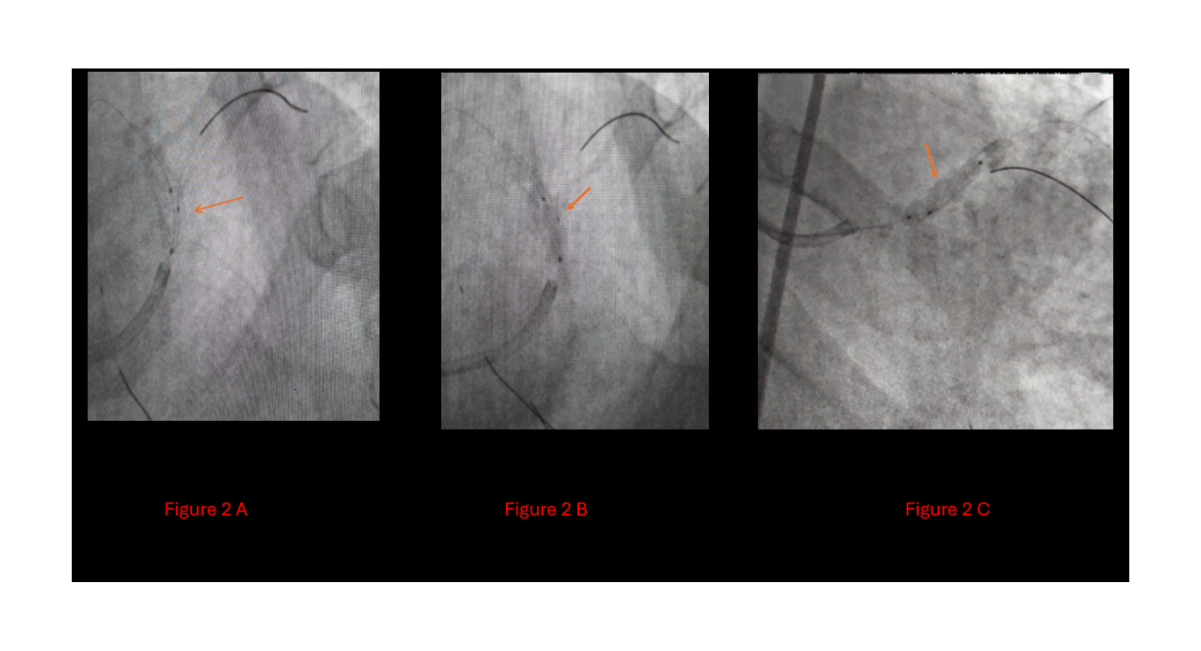

Given the urgent clinical picture and rejection of CABG by multiple centers, a percutaneous coronary intervention (PCI) approach was pursued. The procedure was initiated with the insertion of a 2.0 × 5 mm semi-compliant balloon into the LAD. However, this revealed a bulging calcified plaque between the collapsed stent and the arterial wall, indicating a high risk of arterial perforation. The procedure was temporarily halted due to safety concerns (Figure 2).

Figure 2A: A semicompliant 2*5 balloon was inserted for balloon stent dilatation,

2B: Calcium-deposited bulge,

2C: Indicating a high risk of perforation with the ongoing procedure